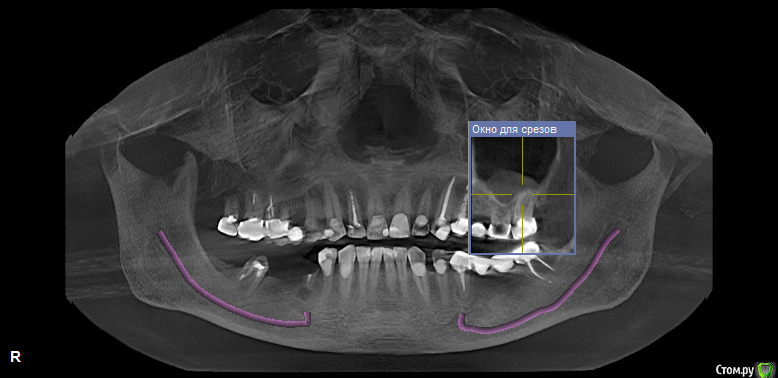

vpaoli Опубликовано 29 февраля, 2016 Поделиться Опубликовано 29 февраля, 2016 (изменено) Посыпались зубы... , что говорят имплантологи-хирурги известно - все удалить и заменить. Хотелось бы получить мнение терапевтов.Под вопросом зубы 16-17, 26-27 и 47. С 45-47 слетел мост, 26-27 после чистки ниткой, у нитки гнилостный запах, над ними в гайморовой пазухе большая киста (видимо как говорят стоматологи онтодогенного происхождения). 47 сидит очень крепко, красноватого цвета, видимо резорцированный и хрупкий. подскажите, можно ли хоть какой то из них лечить?Еще вопрос - над 26, 27 киста в гайморовой пазухе, это опасно или лучше не трогать ? О кисте я узнал только сделав КТ, ранее и сейчас даже не ощущаю ее присутствие.Всех заранее благодарю за высказанное мнение. Изменено 29 февраля, 2016 пользователем vpaoli Ссылка на комментарий

DmitrySH Опубликовано 29 февраля, 2016 Поделиться Опубликовано 29 февраля, 2016 Лучше выложите ссылку на КТ целиком. По данным скриншотам верхние лечить, а нижний 50/50 1 Ссылка на комментарий

faity Опубликовано 1 марта, 2016 Поделиться Опубликовано 1 марта, 2016 Если по этим срезам смотреть, то я бы 1.8, 1.6, 4.5 удалил, остальные лечить 2 Ссылка на комментарий

DmitrySH Опубликовано 1 марта, 2016 Поделиться Опубликовано 1 марта, 2016 Что-то КТ скачалось, но при установке ошибку выдает. По этим скринам, 45 точно удаляется. Это без вариантов. У меня есть некоторые сомнения в 4716 да, возможно удаление, но ракурс не очень удачный. ради него и хотел КТ посмотреть.18. не будет функционировать как зуб.Про мост 47-44 лучше сразу забыть и планировать имплантацию в обл 46, 45. 1 Ссылка на комментарий